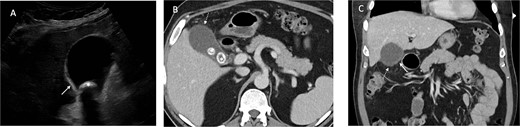

Urgent ultrasound of the upper abdomen and CT abdomen and pelvis were requested. US revealed multiple gallbladder calculi and a 15 mm non-mobile calculus in the neck, and asymmetric thickening of the gallbladder wall suggestive of chronic calculous cholecystitis (Fig. 1). CT showed

An inflamed appendix with peri-appendiceal stranding and a complex 23 × 20 × 27 mm collection at the apex of the appendix with opposed loop of small bowel with mural thickening

Acute cholecystitis with some areas of the gallbladder wall showing no enhancement (Fig. 2)

Ultrasound demonstrates gallbladder wall thickening (solid white arrow in A) and gallstone (* in A). Contrast enhanced CT of the abdomen in portal venous phase axial (B) and coronal (C) planes demonstrate gallbladder wall thickening (solid white arrow in C) and area of nonenhancing wall (dashed white arrow in B and C) and gallstones (* in B).